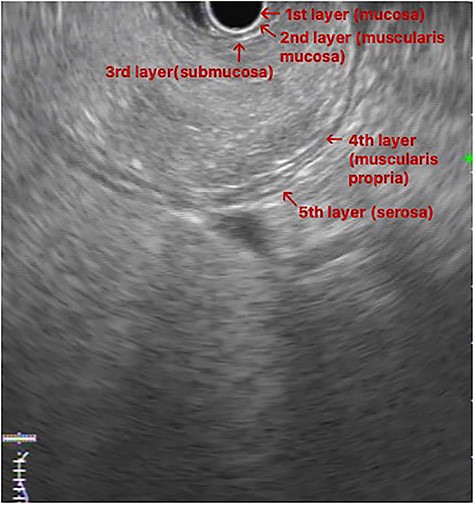

EUS image: homogeneous and hyperechoic lesion in submucosa layer.

An upper GI endoscopy revealed a large subepithelial mass arising from the posterior wall of the gastric antrum, occupying more than 50% of the lumen, soft when pressed with biopsy forceps. The biopsies were non-diagnostic. Additionally, a contrast-enhanced computed tomography (CT) demonstrated a well-defined lesion of the antrum, measuring 8 × 3 cm, non-contrast enhancing and with uniform adipose density, highly suggestive of lipoma (Fig. 1). Endoscopic ultrasound (EUS) also showed a homogeneous and hyperechoic lesion limited to the submucosa (Fig. 2), supporting lipoma diagnosis.

Abdominal CT is the imaging study of choice and highly specific. In the case of gastric lipoma, it strongly suggests the diagnosis by visualization of a well-circumscribed homogeneous mass with fat density ranging between −80 and −120 Hounsfield units. These values are considered pathognomonic and suggest a diagnosis of gastric lipoma, by falling in the expected value range for adipose tissue [4, 5]. EUS is another useful imaging study to confirm the hypothesis of gastric lipoma. By EUS, gastric lipomas appear as homogeneous and hyperechoic lesions from the third layer of the gastric wall [7, 10]. Our patient was diagnosed on endoscopy and confirmed with CT and EUS.